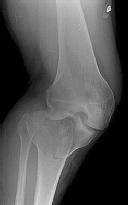

Figures 1 through 3 are the radiographs of a 25-year-old man who is brought to the emergency department after a motorcycle collision. He is complaining of isolated knee pain. Examination reveals swelling, popliteal ecchymosis, joint line pain, and limited knee joint motion. His pulses and sensation are normal.

**CLINICAL SITUATION**